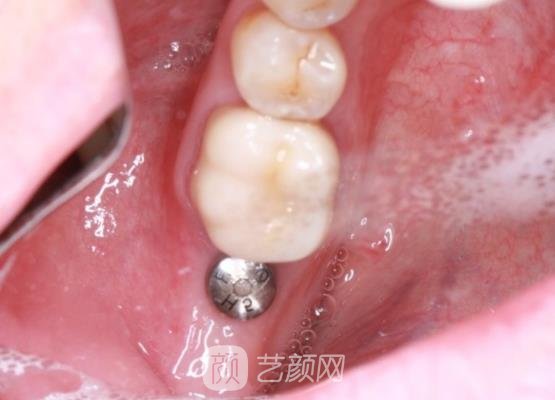

然后医生又对我的牙齿情况进行了检查,拍了口腔全片以后,又按照我的牙齿大小帮我制定了适合我的种植牙手术方案,接下来就开始了手术,手术也是比较方便的,短短几个小时就结束了,并没有浪费我很多的时间,这是我没有想到的。

结束手术时,我的牙龈处还有一些肿胀的情况,疼痛的感觉也是有一些的,医生随后对我的牙齿情况进行了的检查,然后给我开了一些消炎药让我定时服用。